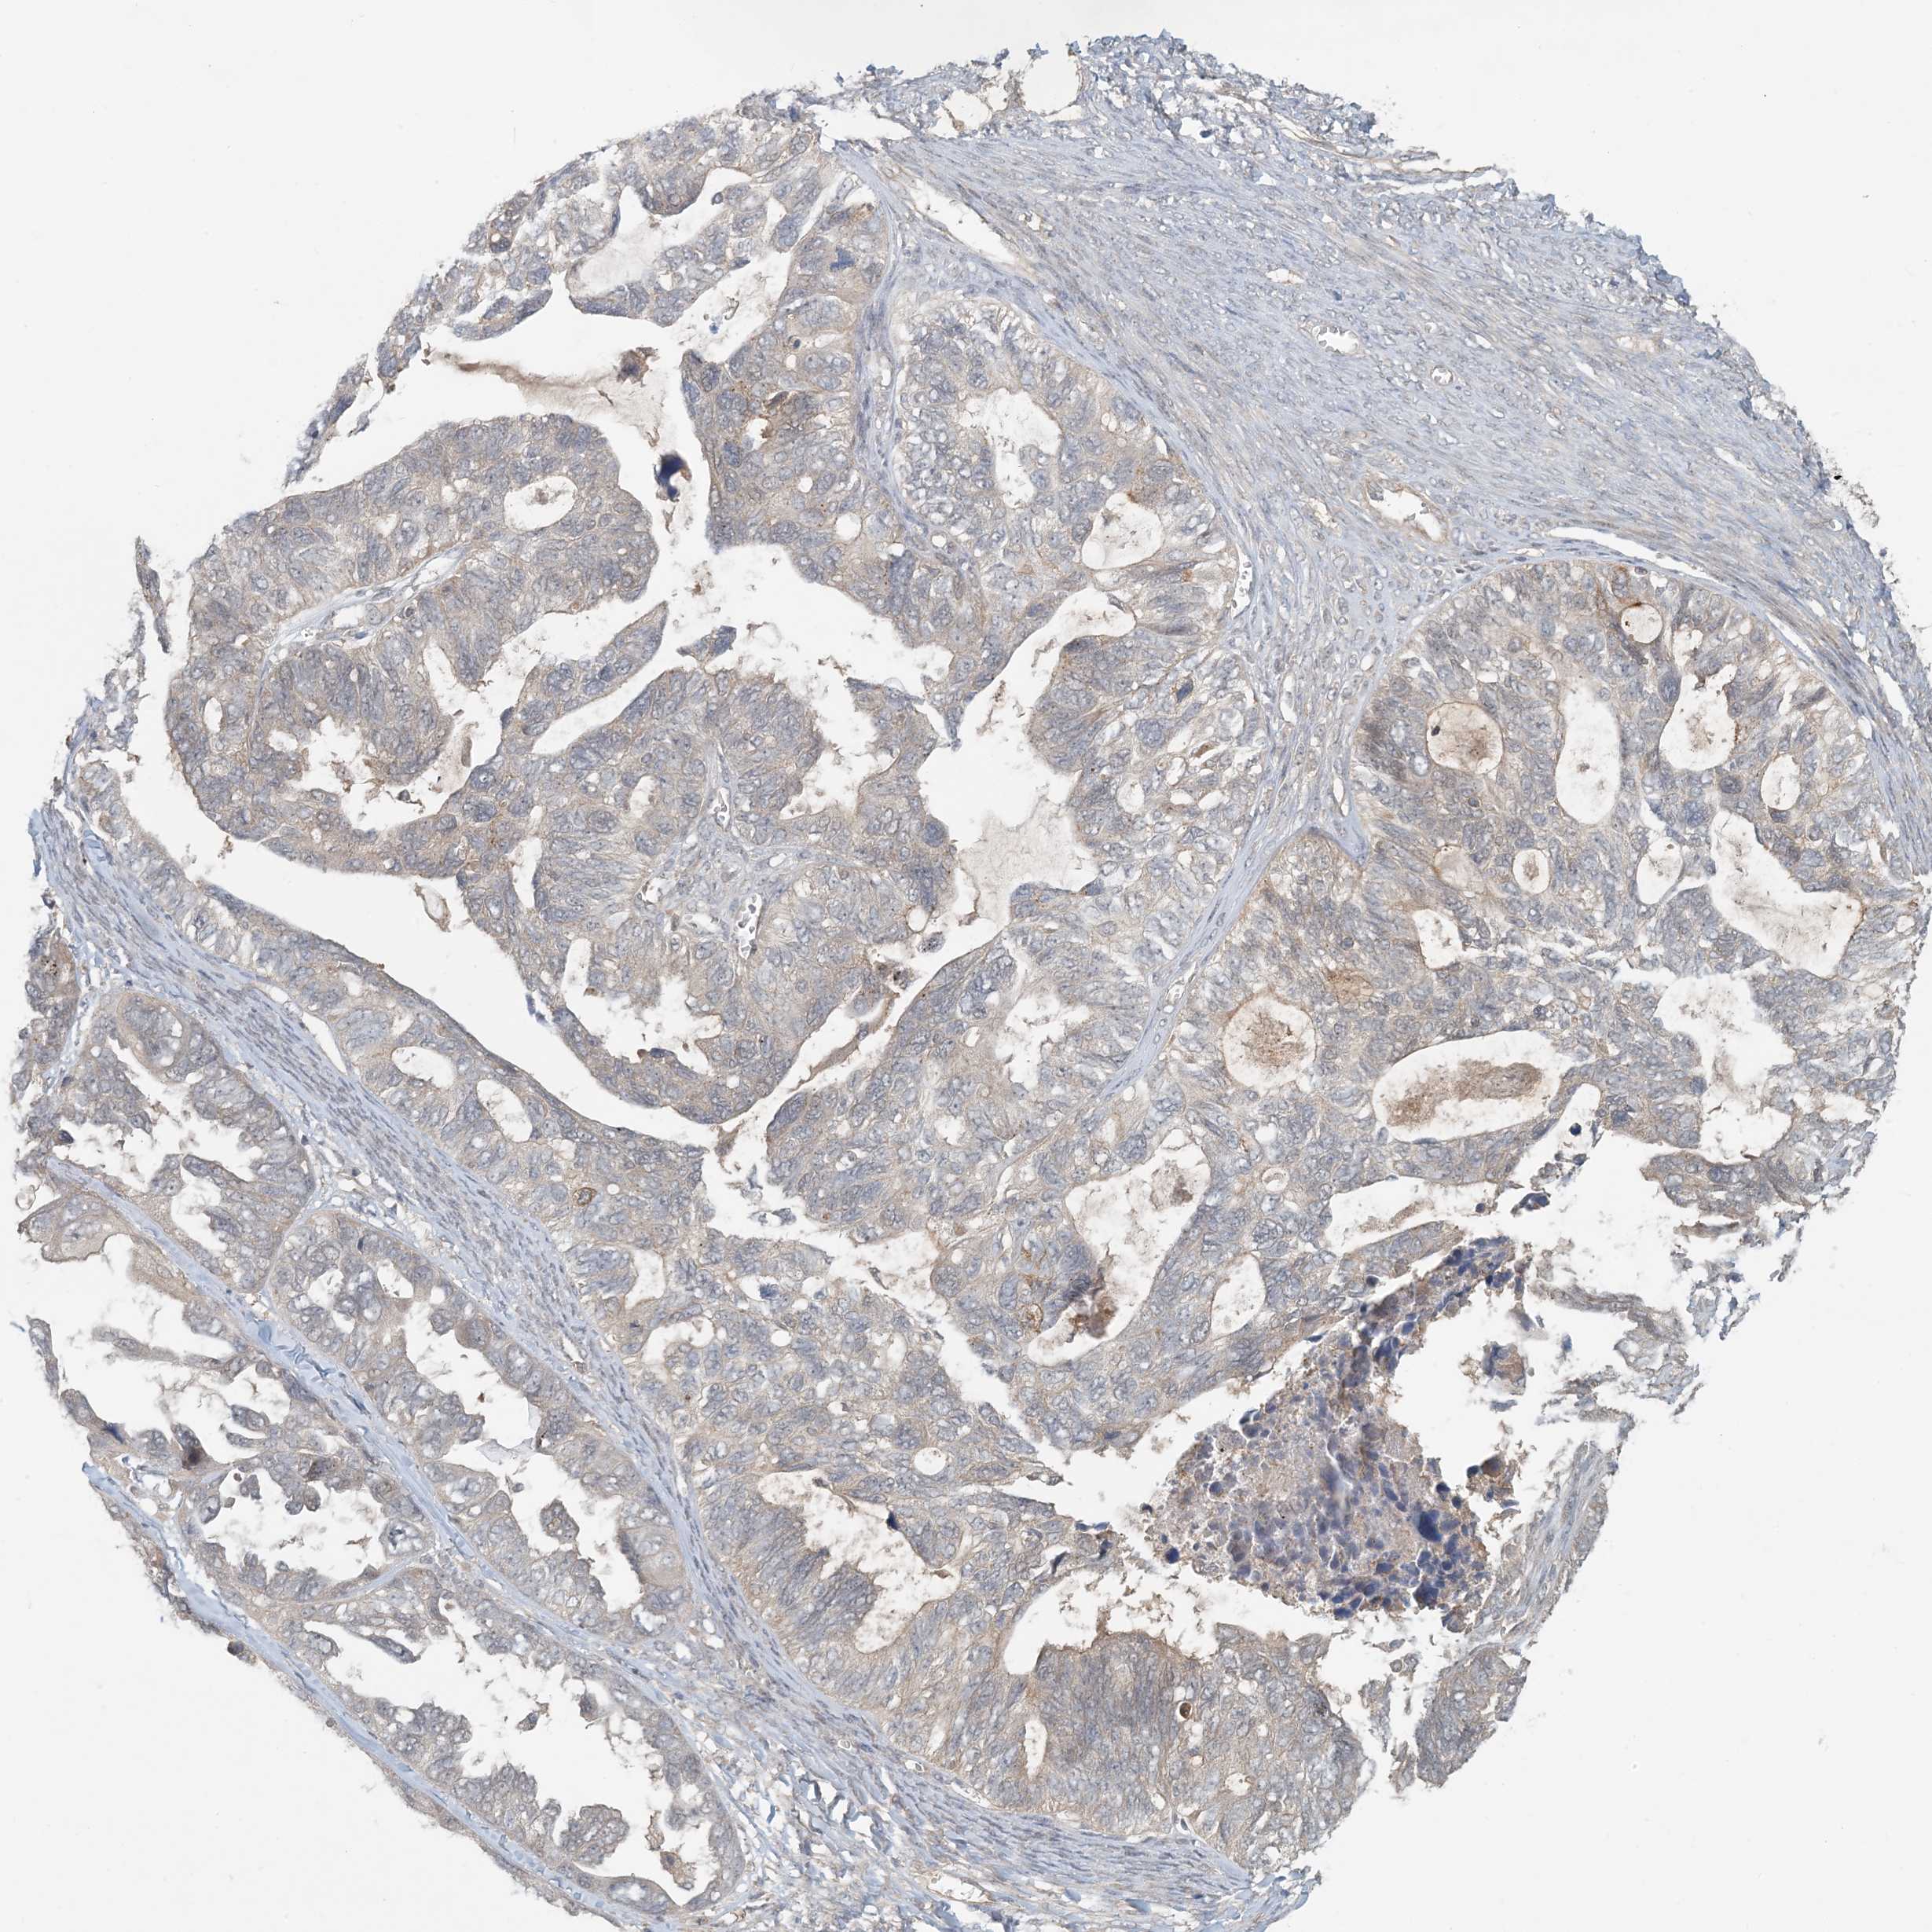

OVARIAN CANCER - Protein expressioni

A mouse-over function shows sample information and annotation data. Click on an image to view it in a full screen mode. Samples can be filtered based on level of antibody staining by selecting one or several of the following categories: high, medium, low and not detected. The assay and annotation is described here.

Note that samples used for immunohistochemistry by the Human Protein Atlas do not correspond to samples in the TCGA dataset.

Antibody stainingi

Antibody staining in the annotated cell types in the current human tissue is reported as not detected, low, medium, or high, based on conventional immunohistochemistry profiling in selected tissues. This score is based on the combination of the staining intensity and fraction of stained cells.

Each image is clickable and will lead to virtual microscopy that enables deeper exploration of all samples and also displays staining intensity scores, fraction scores and subcellular localization as well as patient and tissue information for each sample.

Antibody HPA034785

Antibody HPA034786

Staining

High

Medium

Low

Not detected

Intensity

Strong

Moderate

Weak

Negative

Quantity

>75%

75%-25%

<25%

None

Location

Nuclear

Cytoplasmic/membranous

Cytoplasmic/membranous,nuclear

Cystadenocarcinoma, serous, NOS